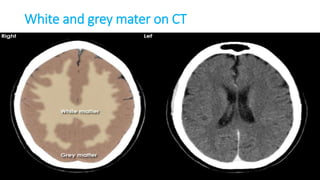

GREY VS WHITE

• The CNS has two kinds of tissue: grey matter and white matter.

• Grey matter contains most of the brain's neuronal cell bodies.[outside]

• White matter is made of axons connecting different parts of grey matter to

each other[inside]

CordBrain

White and grey mater on CT

White and grey mater on MRI

T1 T2